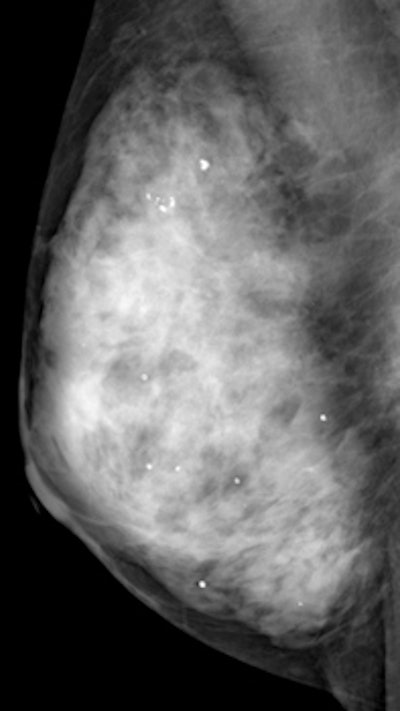

Mammography image of a dense breast. Although mammography is the only proven method of screening that reduces mortality, it is inaccurate in dense breasts, but adjunctive ultrasound can help. Image courtesy of Martin Yaffe, PhD.For this study, the researchers started with a population of 72,998 asymptomatic women ages 40-49 at 42 study sites across 23 prefectures in Japan. Eligible women had no history of any cancer in the previous five years and were expected to live for more than five years.